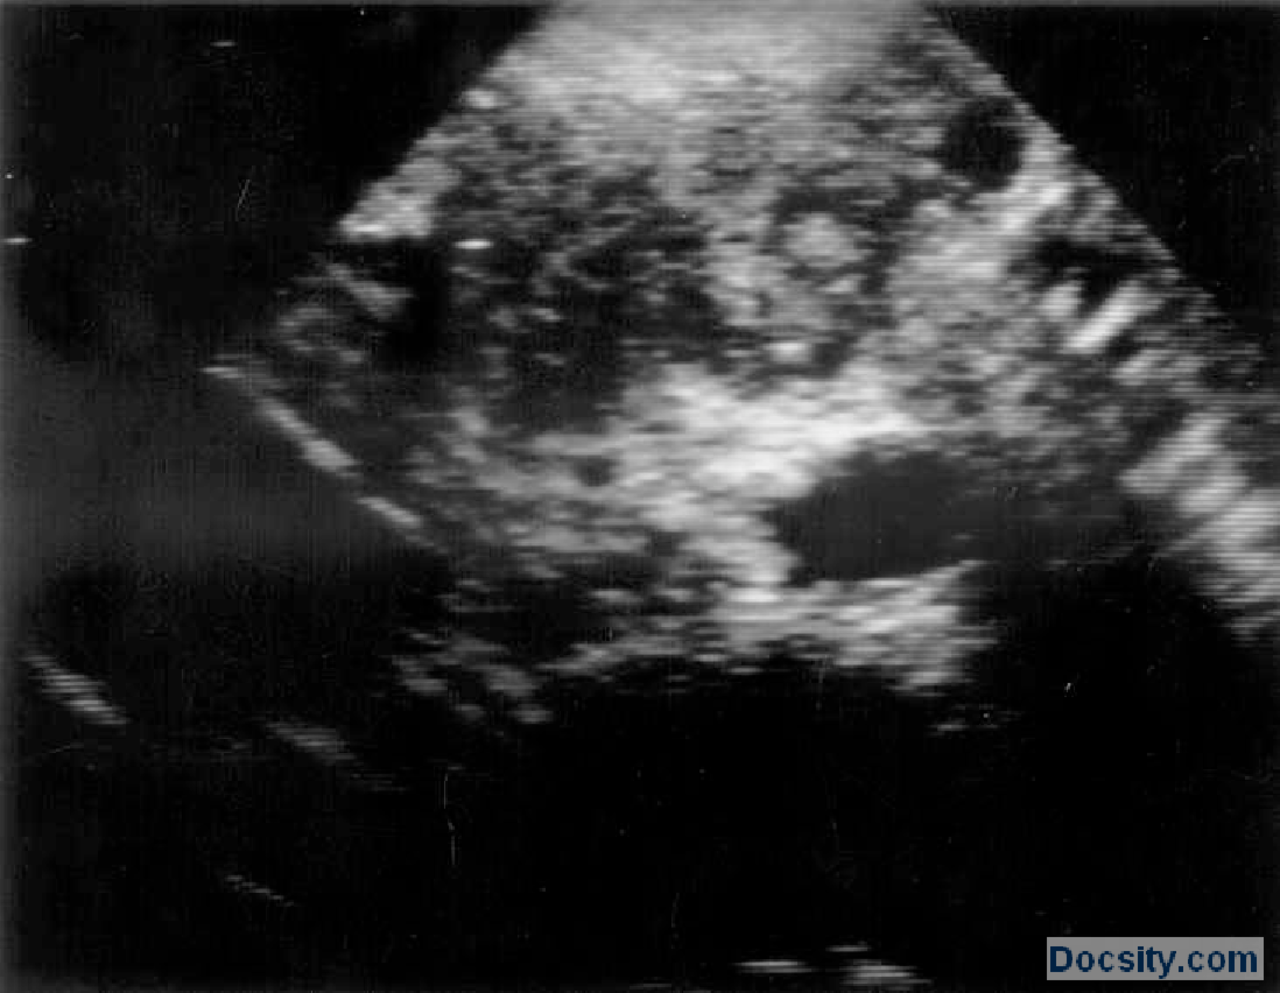

From www.docsity.com

Ultrazvuk snimciVezbeRadiologijaMedicina 6 Vežbe' predlog Radiologija Docsity Petrova Ultrazvuk Zašto je važno redovito provoditi ultrazvuk dojki? Cijena trudničkog ultrazvuka je 150,00kn. Nakon toga otišla sam u glavnu zgradu u petrovoj 13 i tamo u podrumu napravila ultrazvuk. 25% žena oboljelo od raka ima rak dojke. Petrova ulica 13, 10000 zagreb ; Rak dojke je najčešće maligno oboljenje u žena. Naš tim stručnjaka koristi ultrazvuk kao orijentacijski i dijagnostički alat. Petrova Ultrazvuk.